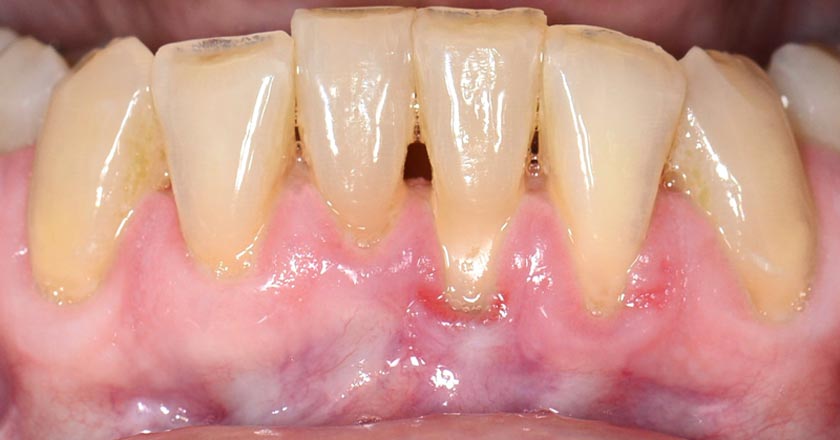

Gum Graft Lower - Before And After

Gum graft lower – before treatment

Gum graft lower – after treatment